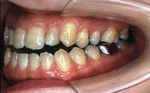

主な不正咬合の種類

このほかにも様々な不正咬合があります。

開校150.jpg

→開校

(上下の歯があたらない)→下顎前突(受け口)

過蓋咬合150.jpg

→過蓋咬合

(下の歯が見えない)